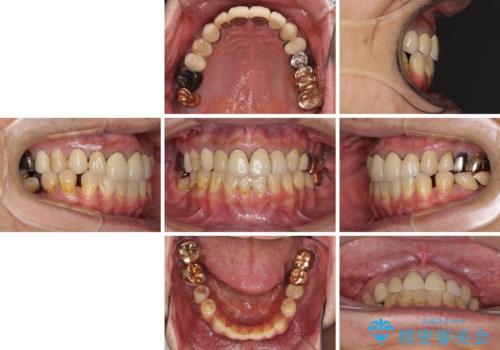

- 抜歯した歯や抜歯が必要と思われる歯を放置したため、奥歯に不快を感じているとのことで来院された患者様です。

右下は奥歯が抜歯したスペースを塞いでしまい、左下はブリッジの支台歯の1つが破折している状態でした。

また、下顎前歯にはスペースがあり、コンポジットレジンでスペースを閉じている状態だったので、前歯のスペースを解消しつつ、奥歯にスペースを獲得するよう矯正治療を行うこととしました。

並行して左下にはインプラントを埋入し、上顎臼歯部の気になる部分も根管治療などを進めて行き、矯正治療を終えると同時に補綴治療を行うこととしました。